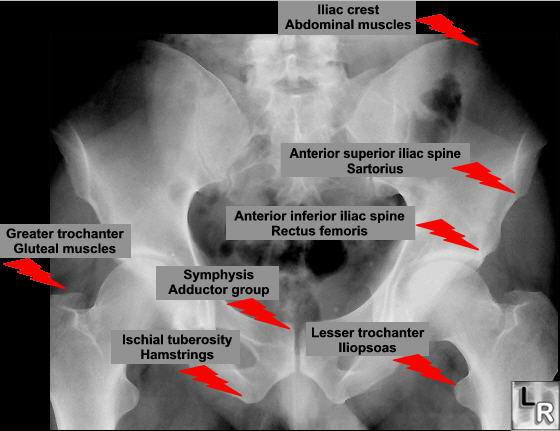

Any of the major muscle attaching to the pelvis or proximal femur may pull off at their attachment. This is classically a sporting injury, resulting from those resulting from extreme, unbalanced, often eccentric muscular contractions.

Once healing starts these lesions may mimic the appearance of an osteosarcoma, unfortunately so may the histology.

Anterior-Superior Iliac Spine Avulsion

This is the attachment of the sartorius and tensor fascia lata muscles.